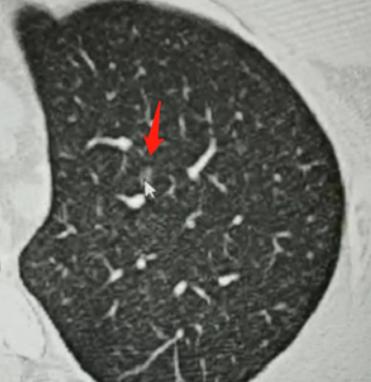

昨天接诊了个23岁的小伙子,一进诊室眼眶就通红,坐下没两句话就带着哭腔问我:“乔医生,我是不是快不行了?您说实话,我还剩几个月时间?” 这话一出来,我就知道他肯定是被检查结果吓懵了。 我先示意他别慌:“先稳住情绪,别自己吓自己,把你的片子给我看看,咱们慢慢说。” 接过他手里的检查报告和影像片,我仔细逐帧翻看,这才发现他肺里长了十几枚磨玻璃结节,难怪小伙子会这么害怕,换谁查出这么多结节,心里都得打鼓。 反复确认片子细节,又对照了他之前几次的复查记录后,我抬头肯定地跟他说:“你这情况一点危险都没有,踏踏实实过好日子就行,完全不影响寿命。” 小伙子愣了一下,显然没敢相信这话。 我接着跟他解释,这里面最大的那枚结节,考虑是原位癌性质,但他几次复查下来,结节都没有任何变化,这说明它基本不生长,恶性程度也几乎可以忽略不计。 对于这种多发的磨玻璃结节,咱们宁愿耐心观察随访,也不能盲目做手术乱切,毕竟手术对身体伤害太大,反而得不偿失。 我跟他说,我这儿有不少和他情况一样的病人,都是多发磨玻璃结节,跟着我随访了十几年、二十年,结节一直没变化,照样正常工作、结婚生子,过着和普通人一样的生活。我让他半年过来复查一次,有我盯着,绝对不会耽误病情。 我特意叮嘱他,别因为这些密度淡的小结节打乱自己的生活,该上学上学、该工作工作,不用整天揪着这事焦虑。真要是哪次复查发现某个结节有细微变化,咱们再针对性处理,到时候治疗效果和现在手术是一样的,根本不危及生命。 听我说完这些,小伙子紧绷的肩膀终于松了下来...... 其实想跟有多发肺结节的朋友们说一句,遇到这种情况别慌也别害怕。结节不等于癌症,没变化就安心观察,有问题咱们就及时处理。日子都是一步步过的,不用被未知的恐惧困住,慢慢走,总能顺利通关。[玫瑰][作揖]